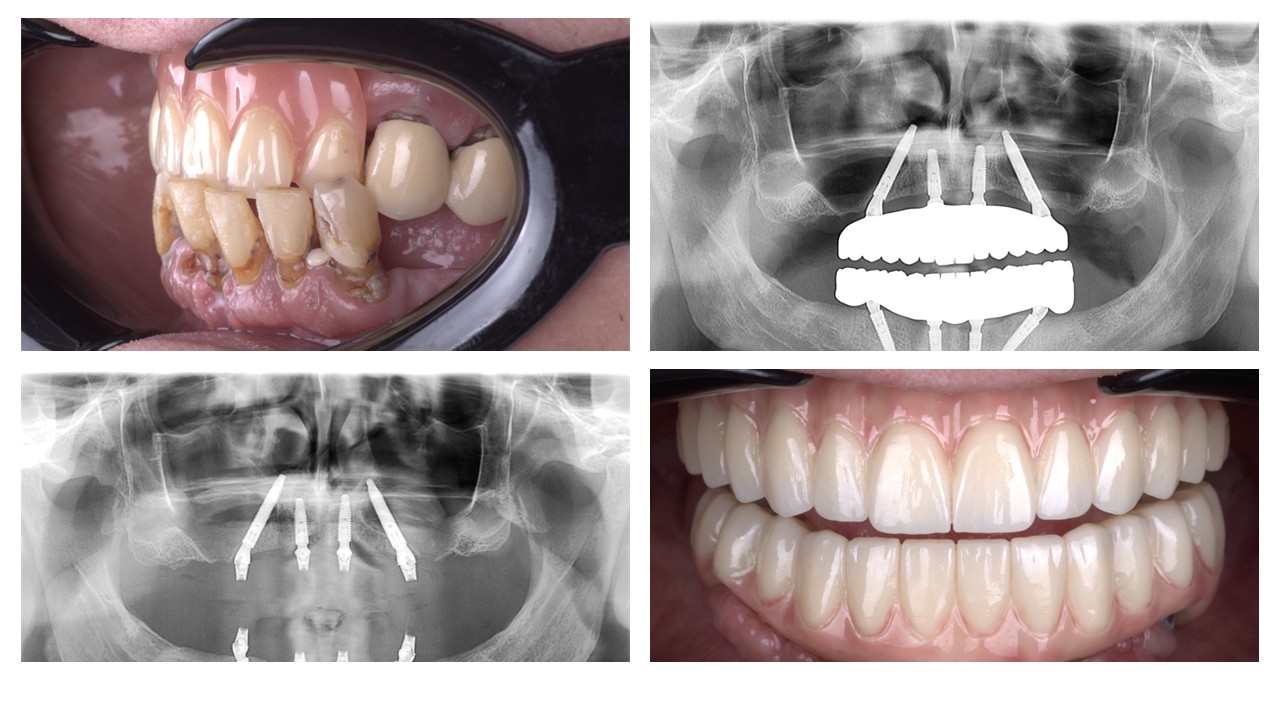

Level 1 Case: Socket shield technique

initial state Surgical stage after initial healing Final Restoration The future of the aesthetic zone isn’t found in a bottle of bone substitute; it is found in the meticulous preservation of the patient’s own anatomy.